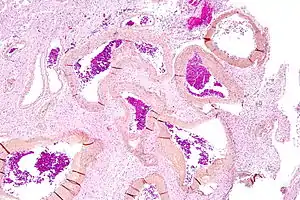

![]() | |

| Micrograph of an arteriovenous malformation in the brain. HPS stain. | |